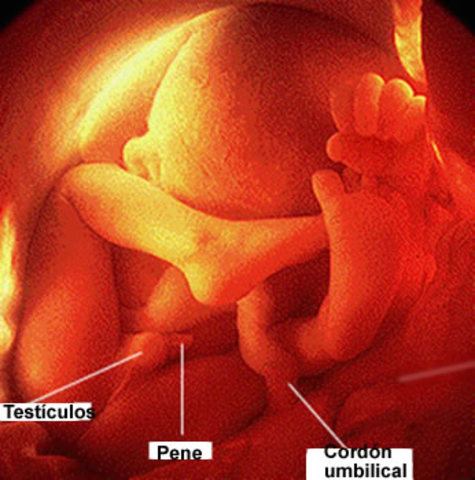

Las uñas empiezan a crecer y los huesos a endurecer, los riñones producen orina y los órganos sexuales empiezan a desarrollarse.

El vello o lanugo se cae, y en el sexo masculino los testículos inician el descenso al escroto.